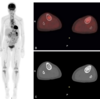

Melanoma

Pneumonitis

82